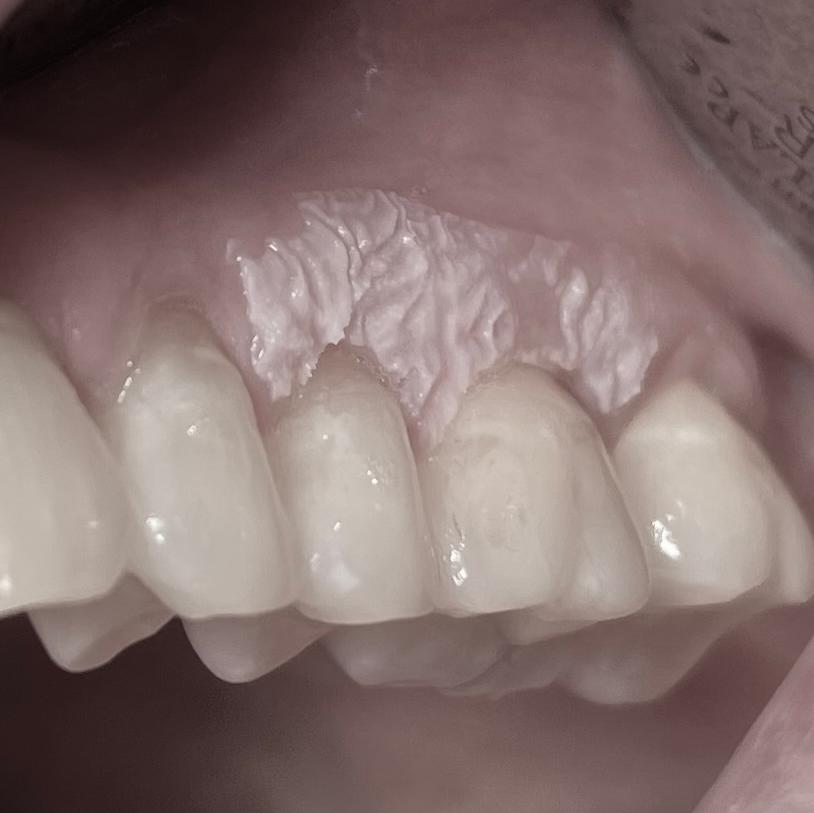

Cursus Composietrestauratie in het front

Na een inleidende presentatie, volgt een live demo en hands-on training waarbij de simulatie van een aantal getoonde clinical cases aan bod komen. Het bij de cursus gebruikte materiaal is van IPS Empress Direct.

Onder begeleiding van onze vaste docent Arend van den Akker krijg je veel praktische tips, en kun je deze, na de hands-on training, meteen toepassen in de praktijk.

Na de cursus krijg je de gebruikte cursuskit met enige toebehoren mee, evenals een overzicht van de gebruikte materialen.

De volgende onderwerpen komen aan bod gedurende deze 1- daagse cursus:

• De preparatie nader toegelicht

• De maltechniek nader bekeken (waxup intra- en extraoraal)

• Biotypes en de implicatie hiervan voor de praktijk

• Kleurbepaling en de noodzaak van fotografie, DSD

• Een determinatiesysteem voor karakterisering

• Diastemen

• Fluorescentie en opalescentie (en hoe krijg ik dat in de restauratie?)

• Vorm en oppervlakte structuur in relatie tot de afwerking

• Facings

• Multiple layering met karakterisering en opalescentie

Leerdoelen

• Kan de geleerde tips and tricks toepassen in de praktijk

• Heeft geleerd om hoogwaardige en esthetische composietsrestauraties te kunnen vervaardigen in het front